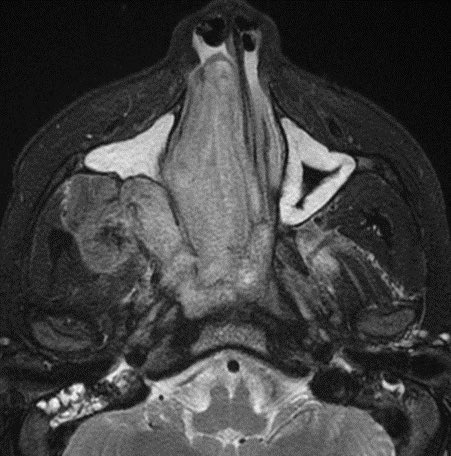

⭐️ Classic case: what’s the most likely diagnosis in this 12 y/o M presenting with stuffy nose and epistaxis? #ENT #Peds #medicine #radres #futureradres #Neurology #neurosurgery @ASHNRSociety @Radiopaedia

⭐️ Classic case: what’s the most likely diagnosis in this 12 y/o M presenting with stuffy nose and epistaxis? #ENT #Peds #medicine #radres #futureradres #Neurology #neurosurgery @ASHNRSociety @Radiopaedia